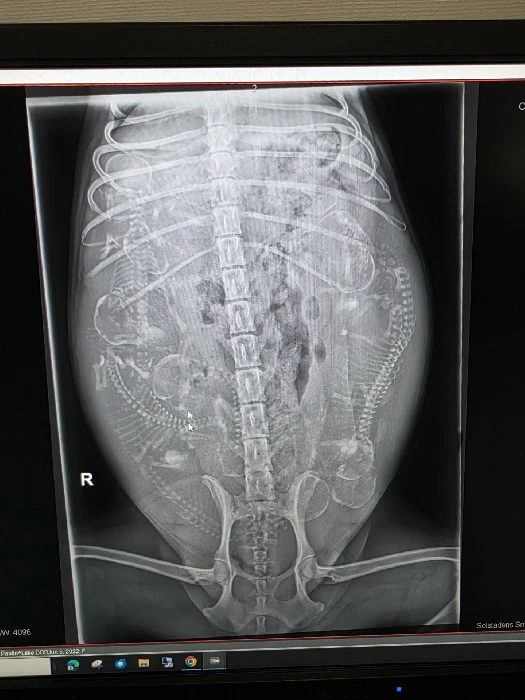

Idag tog vi röntgenbilder på Lillies valpmage! HemValpblogg I Valpblogg 22.07.2025 Vetrinären såg 🐶🐶🐶🐶🐶🐶🐶🐶🐶9st valpat!!! Lämna ett svar Avbryt svarDin e-postadress kommer inte publiceras. Obligatoriska fält är märkta *Kommentar * Namn * E-postadress * Webbplats Spara mitt namn, min e-postadress och webbplats i denna webbläsare till nästa gång jag skriver en kommentar. Författare paulin.skold@gmail.com Relaterade inlägg I Valpblogg ❤️-tik 2025-08-08 2 Läs upp allt I Valpblogg 🖤-Hane 2025-08-06 0 Svart/Grå hane 🩶 Läs upp allt I Valpblogg 💙-Hane 2025-08-06 2 Mörkblå hane 💙 Läs upp allt I Valpblogg Veterinären 2025-08-02 0 Vi har i dagarna två varit in med Lillie till vetrinären på grund av inflamation i livmodern. Hon hade 164 i sänka... Läs upp allt I Valpblogg Dagens favoritbilder! 2025-07-27 0 Se upp för sockerchock! Läs upp allt I Valpblogg Spa Hagalund 2025-07-27 0 Är man 9valpars mor har man rätt till ”det lilla extra”…spa Hagalund Läs upp allt Inläggsnavigering Föregående inläggNästa inlägg